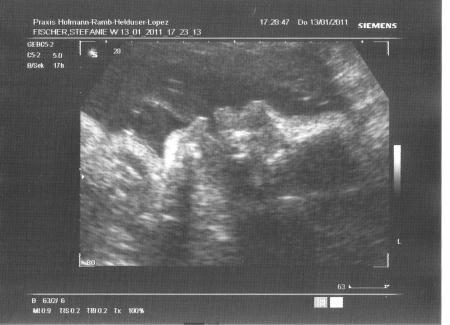

Heute war ein guter Tag! Waren heute mal wieder beim FA zur Vorsorge, da auch der 3. US anstand. Sonst mach ich die VU ja meist bei der Hebamme. Also der kleine Mann ist superfit, bleibt auch definitiv bei nem Jungen! Er wiegt jetzt ca. 1900 g (ganz ordentlich, meine Tochter hat zu diesem Zeitpunkt 400 g weniger gewogen!!!) Und er hat nen Dickkopf mit 8,7 cm BPD Na das kann was werden bei der Geburt... Ein schönes Profilbild haben wir auch bekommen, vielleicht scan ich es noch ein nachher. Mumu ist auch geschlossen, GMH steht, er liegt in SL, was will man mehr. Nicht so dolle ist mein Gewicht (aber zum Glück sind da Winterklamotten und schwere Schuhe mitgerechnet ) und im Urin war auch schon wieder Zucker. Außerdem haben wir heute den Hochzeitstermin festgemacht! Ab dem 28.5. sind wir dann also verheiratet! GLG Steffi

Mein kleiner Mann im Profil, mit offenem Mündchen, er war grad am Trinken, sooo süß!

Bild zu